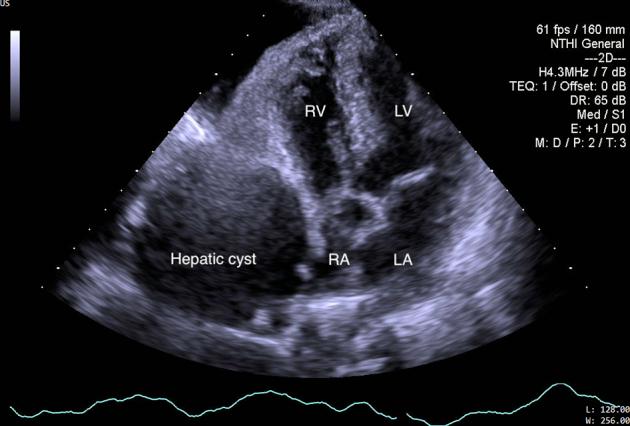

A Case of Hepatic Cyst-Induced Internal Jugular Venous Thrombosis.

• Echocardiography can demonstrate hepatic cyst–induced right atrial compression. • Hepatic cyst–induced blood flow stasis can cause internal jugular venous thrombus. • Laparoscopic deroofing of hepatic cysts is a safe and effective treatment.

• 超声心动图可显示肝囊肿所致的右心房受压。